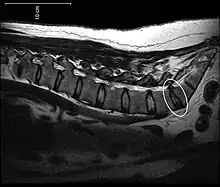

Spinal disc protrusion visible in MRI

[1] A disc protrusion is a medical condition that can occur in some vertebrates, including humans, in which the outermost layers of the anulus fibrosus of the intervertebral discs of the spine are intact but bulge when one or more of the discs are under pressure.

Many disk abnormalities seen on MRI that are loosely referred to as "herniation" are actually just incidental findings. These may be unrelated to any symptoms and are just bulges of the anulus fibrosus. Jensen and colleagues, in an MRI study of the lumbar spine in 98 asymptomatic adults, found that in more than half, there was a symmetrical extension of a disc (or discs) beyond the margins of the interspace (bulging). In 27 percent, there was a focal or asymmetrical extension of the disc beyond the margin of the interspace (protrusion), and in only 1 percent was there more extreme extension of the disc (extrusion or sequestration). These findings emphasize the importance of using precise terms in describing the imaging abnormalities and evaluating them strictly in the context of the patient's symptoms.[1]

A disc protrusion may progress to a spinal disc herniation, a condition in which there is a tear in the anulus fibrosus.[2] The most common area to have a disc protrusion is in the Lumbar Spine, specifically L-5.[2]